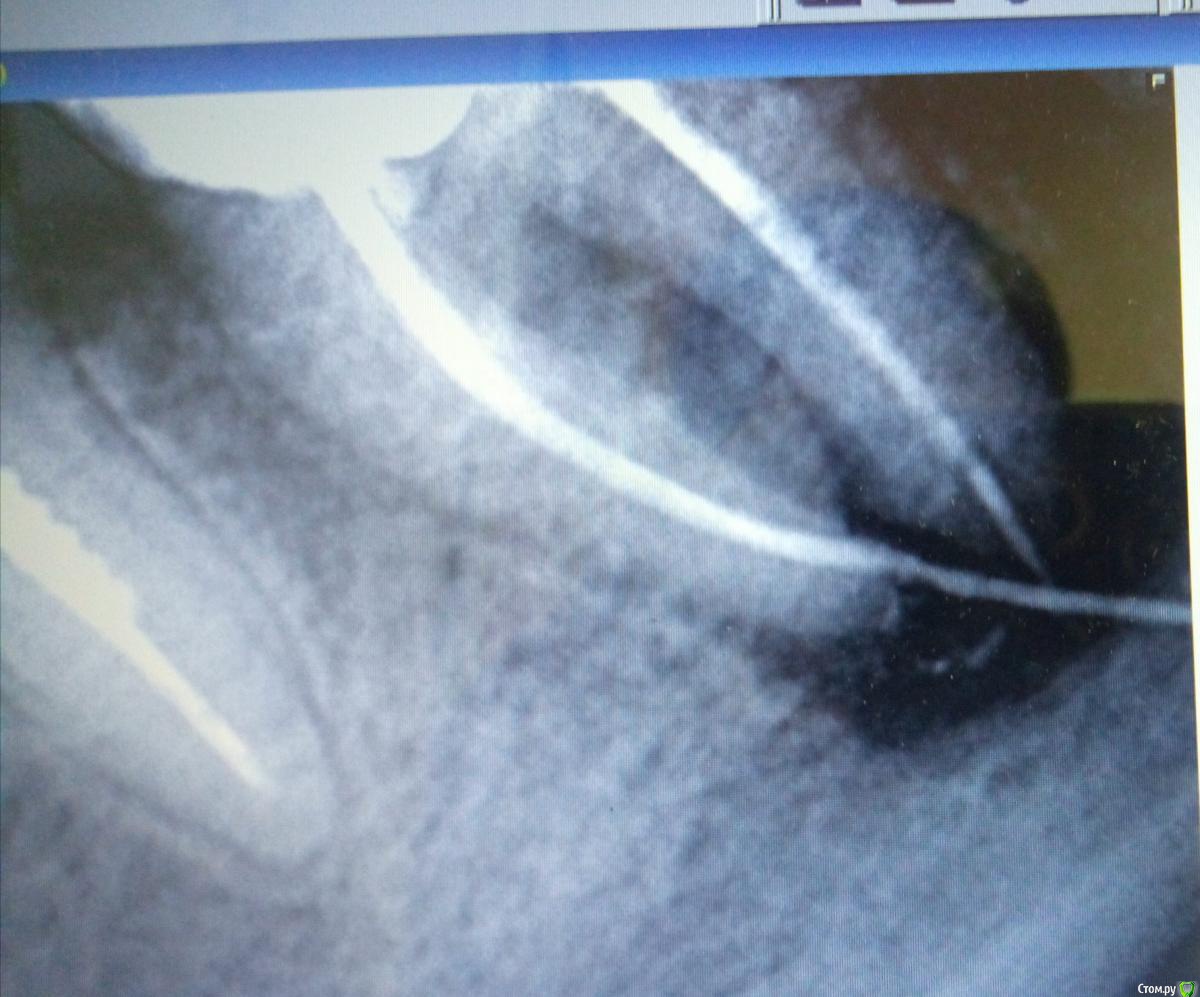

MVZ Опубликовано 25 марта, 2019 Поделиться Опубликовано 25 марта, 2019 37ой зуб. Лечили пол года назад. Был глубокий скол зуба, врач решил удалить нервы, хотя он и не болел. Проделал он всю операцию успешно, запломбировал, сделал снимок и остался доволен результатом. Через месяц начал зуб болеть при касании все сильней и сильней, так что аж челюсть заболела. Пришла к тому же врачу, он рассказал мне сказку, что это зуб мудрости проснулся и толкается, надо попить антибиотик, и на пятый день пойти к другому врачу на удаление зуба мудрости. Начала пить антибиотик, пришла на пятый день к другому врачу. Он сделал мне КТ и сказал: понятия не имею, при чем здесь зуб мудрости, к тому же он очень сложный, от его удаления вся челюсть опухнет на 2 недели, а зуб болит скорее всего из-за реакции на пломбу и типа сам пройдет, на КТ с ним всё нормально. Ну и немного мне подкорректировал пломбу на этом 37 зубе. На всякий случай. На следующий день стало легче, перестала болеть челюсть. Непонятно, это из-за антибиотиков или из-за корректировки пломбы. но боль при касании зуба не прошла. И ждала я значит, ждала, когда он пройдет. А он не прошел. Боль просто стала терпимой. А вот неделю назад вылез свищ под зубом. Пришла я к третьему доктору. Она сделала снимок, посмотрела и сказала, что понятия не имеет что это такое и что она туда не полезет! Возвращайся, говорит, к первому доктору, пусть он и разбирается по гарантии. Но как-то никакого доверия нет к тому доктору после такого Подскажете может чего-нибудь по снимку? Большое воспаление, мне сказали. А что за белые полосы в продолжение канала?? Ссылка на комментарий

suballex Опубликовано 25 марта, 2019 Поделиться Опубликовано 25 марта, 2019 Чертовщина называется гуттаперчевым штифтом. Ссылка на комментарий

krokomot Опубликовано 25 марта, 2019 Поделиться Опубликовано 25 марта, 2019 Фаил кт конечно объемный, но по результатам могу сказать, в этом зубе 3.7, запломбированы только 2 канала из 3-х, и в медиально-щечном канале выведена гуттаперча за апекс на 8 мм, что делать?, попытаться удалить гуттаперчу через канал, требуется опытный эндодонтист. Если не выйдет, удаление зуба. Боли врядли прекратятся. А удалить гуттаперчивый штифт хирургически никто не возьмется в виду близость нижнеальвеолярного нерва. 1 Ссылка на комментарий